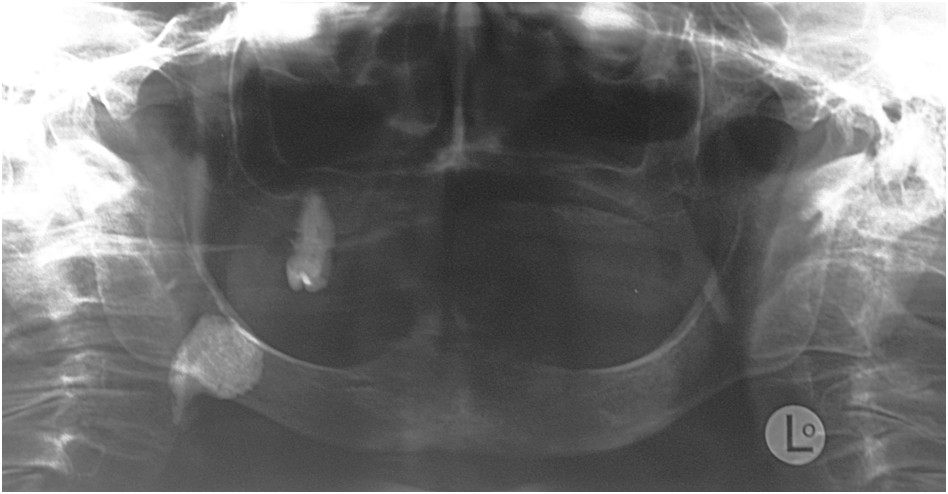

Pacjentka podaje bóle i wygórowanie w okolicy podżuchwowej po stronie prawej zwykle w czasie posiłków. Wynik pantomogramu przedstawiono poniżej. Co jest przyczyną podawanych objawów?